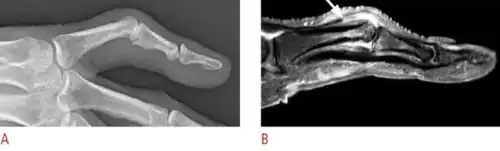

Boutonniere deformity is a deformed position of the fingers or toes, in which the joint nearest the knuckle (the proximal interphalangeal joint, or PIP) is permanently bent toward the palm while the farthest joint (the distal interphalangeal joint, or DIP) is bent back away (PIP flexion with DIP hyperextension). Causes include injury,[1] inflammatory conditions like rheumatoid arthritis, and genetic conditions like Ehlers-Danlos syndrome.[2]

This flexion deformity of the proximal interphalangeal joint is due to interruption of the central slip of the extensor tendon such that the lateral slips separate and the head of the proximal phalanx pops through the gap like a finger through a button hole (thus the name, from French boutonnière "button hole"). The distal joint is subsequently drawn into hyperextension because the two peripheral slips of the extensor tendon are stretched by the head of the proximal phalanx (note that the two peripheral slips are inserted into the distal phalanx, while the proximal slip is inserted into the middle phalanx). This deformity makes it difficult or impossible to extend the proximal interphalangeal joint.

In the evaluation radiographs are used to determine if fractures exist and severity of any hyperextension[3]